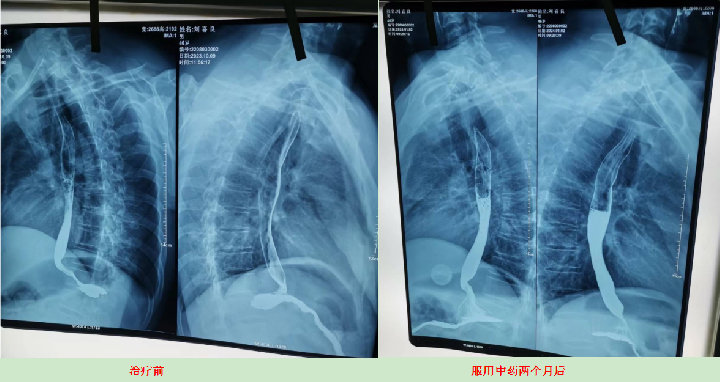

案例4、食道癌两个月清零

患者:刘喜良   男 46岁   食道中段癌

2023年10月9日CT影响报告诊断查出食管壁增厚,管腔狭窄,食管癌。找到陈海林老师使用中医药两个月治疗后CT显示食管各段顺利通过,食管恶性肿瘤治疗后改变。

上图是服用两个月中药的前后对比图